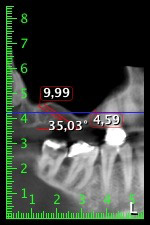

59-годишна пациентка с напреднал стадий на пародонтит описва неприятно чувство и лош вкус в първи квадрант в дисталната зона. Клиничният преглед разкрива силно уголемени пародонтални джобове и напреднала костна атрофия в зона 16 и 14. Рентгенографията потвърждава констатациите (Фиг. 1). Зъби 16 и 14 не могат да бъдат запазени.

Снимка 1: Ортопантомография с костна атрофия в зони 16–14.*